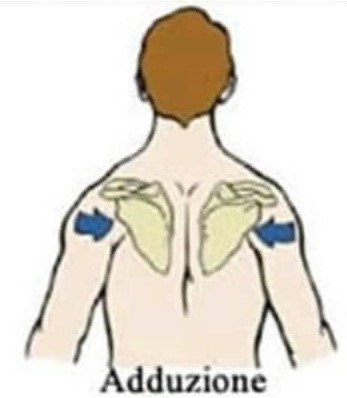

Trapezio medio e muscoli romboidi nella parte superiore della schiena portano le scapole all’indietro per mantenere le spalle ed il petto in una postura corretta. Trapezio e muscoli romboidi indeboliti permettono alle scapole di inclinarsi anteriormente, contribuendo ulteriormente a spalle curve e ad una postura della testa in avanti.